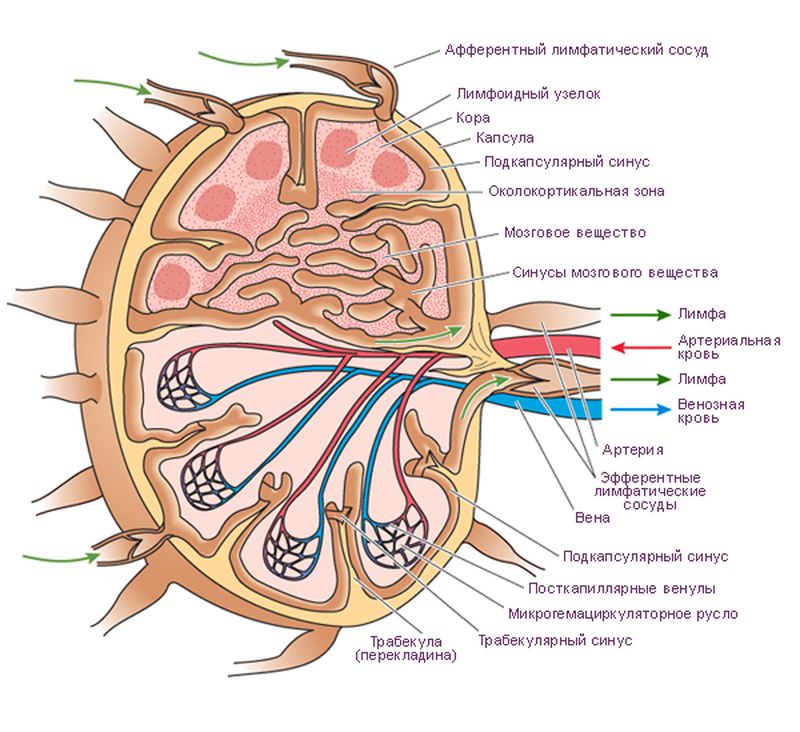

Изображения и схемы: как выглядит лимфа